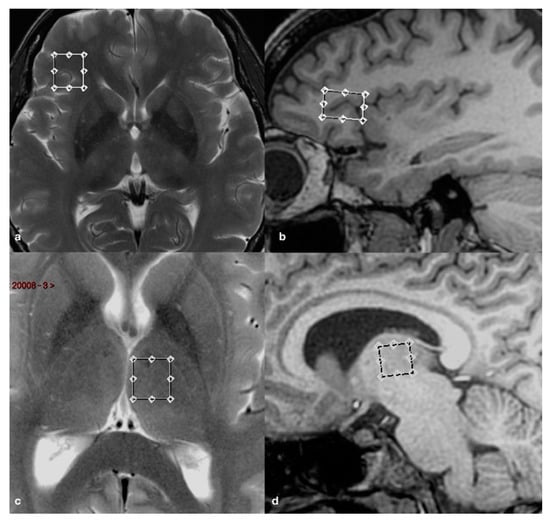

All MR imaging were performed by using a 3.0 Tesla whole-body scanner (Signa EXCITE; GE Healthcare, Milwaukee, Wisconsin) equipped with an 8-channel standard phased array head coil. T2-weighted fast spin echo (FSE) sequences were acquired in the axial and coronal planes, while a 3D T1-weighed fast spoiled gradient recalled echo (FSPGR), with an isotropic voxel, was obtained with reconstructions on the axial and coronal planes. A point resolved spectroscopy (PRESS) pulse sequence (TR 2000 ms; TE 35 ms; 128 acquisitions) was used to generate the spectra of the volumes of interest (VOI; 1.8 and 2.1 cm3). The voxels of interest (VOIs) were placed bilaterally on the thalamus and ventrolateral prefrontal cortex (VLPFC), respectively, using the 3D FSPGR and FSE structural scans as references to avoid sampling contaminations by bone, vascular and cerebrospinal fluid (CSF) structures (Figure 1).

Figure 1. Axial T2-weighted fast spin echo (FSE) and sagittal 3D fast spoiled gradient recalled (FSPGR) images showing voxels of interest (VOIs) placement in the right ventrolateral prefrontal cortex (VLPFC) (a,b) and left thalamus (c,d).